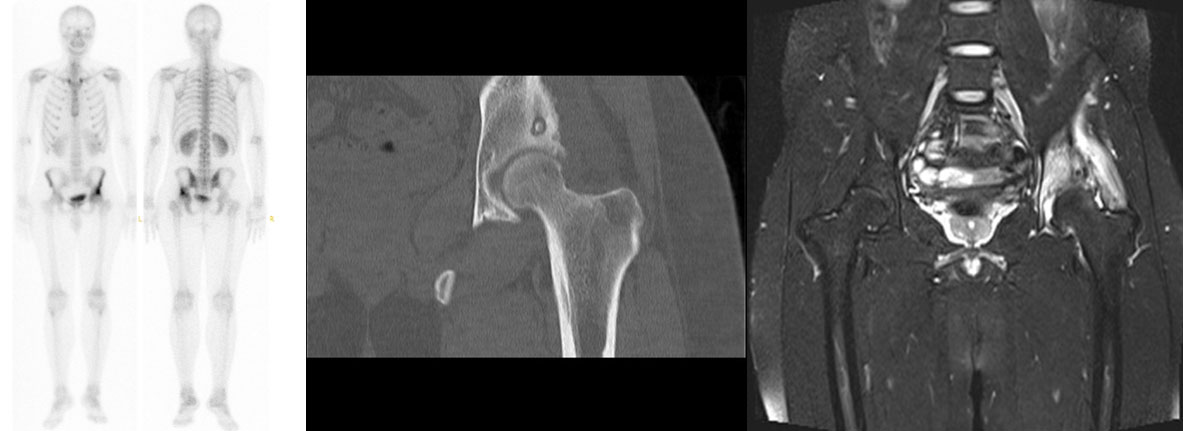

Sol kalça ağrısı nedeniyle başvuran 15 yaşındaki erkek hastada, yapılan tetkikler sonucunda asetabulum yerleşimli osteoid osteoma tespit edildi. Tomografi rehberliğinde radyofrekans ablasyon işlemi uygulanarak, hastanın ağrısı tamamen ortadan kaldırıldı. İşlem sonrası hasta ağrısız bir şekilde taburcu edildi.

İşlem Öncesi:

• Sintigrafide artmış yoğun aktivite

• Tomografide tipik nidus görüntüsü

• MR’da yaygın kemik ve yumuşak doku ödemi

İşlem Esnası:

• Cihazın tümöre (nidus) bitişik yerleştirilmesi ve yakma esnasında takip edilmesi